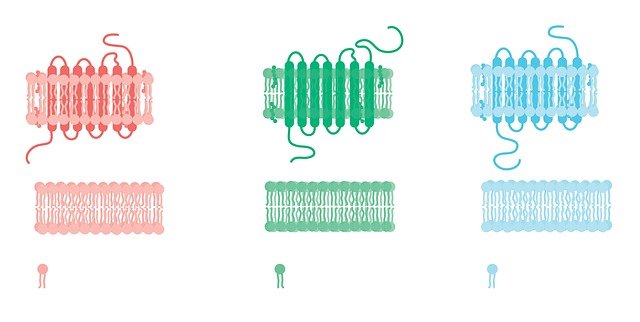

Predicting protein structure can help researchers better understand how proteins work and speed up treatment for diseases such as COVID-19 and cancer. ...

Researchers at Washington University in St. Louis reported novel approach for the treatment of certain neurological disorders. Neu...